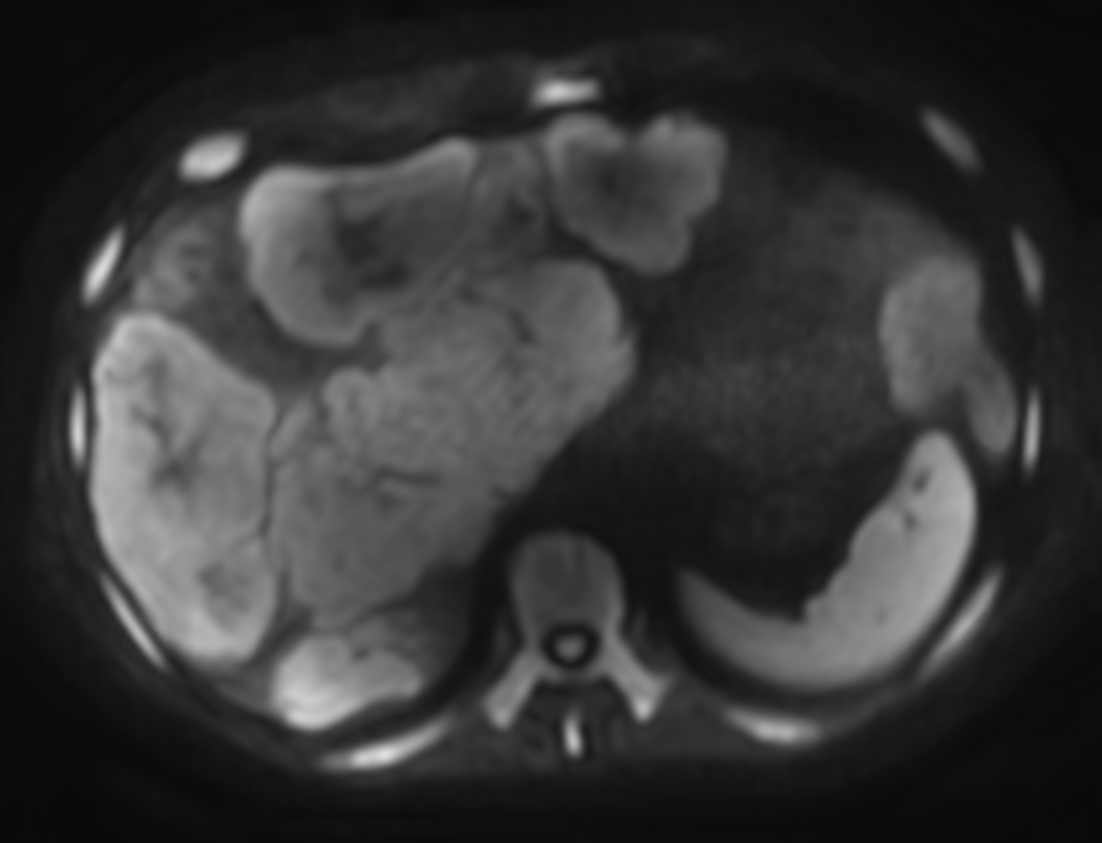

Patient with liver metastasis. The ExamCard includes techniques for efficient fat-free imaging over large field-of-views (mDIXON XD), a procedure for non-invasive liver fat quantification (mDIXON Quant), a multi-phase contrast-enhanced sequence (4D FreeBreathing) to improve imaging confidence and Compressed SENSE to accelerate the entire exam.

T2w TSE